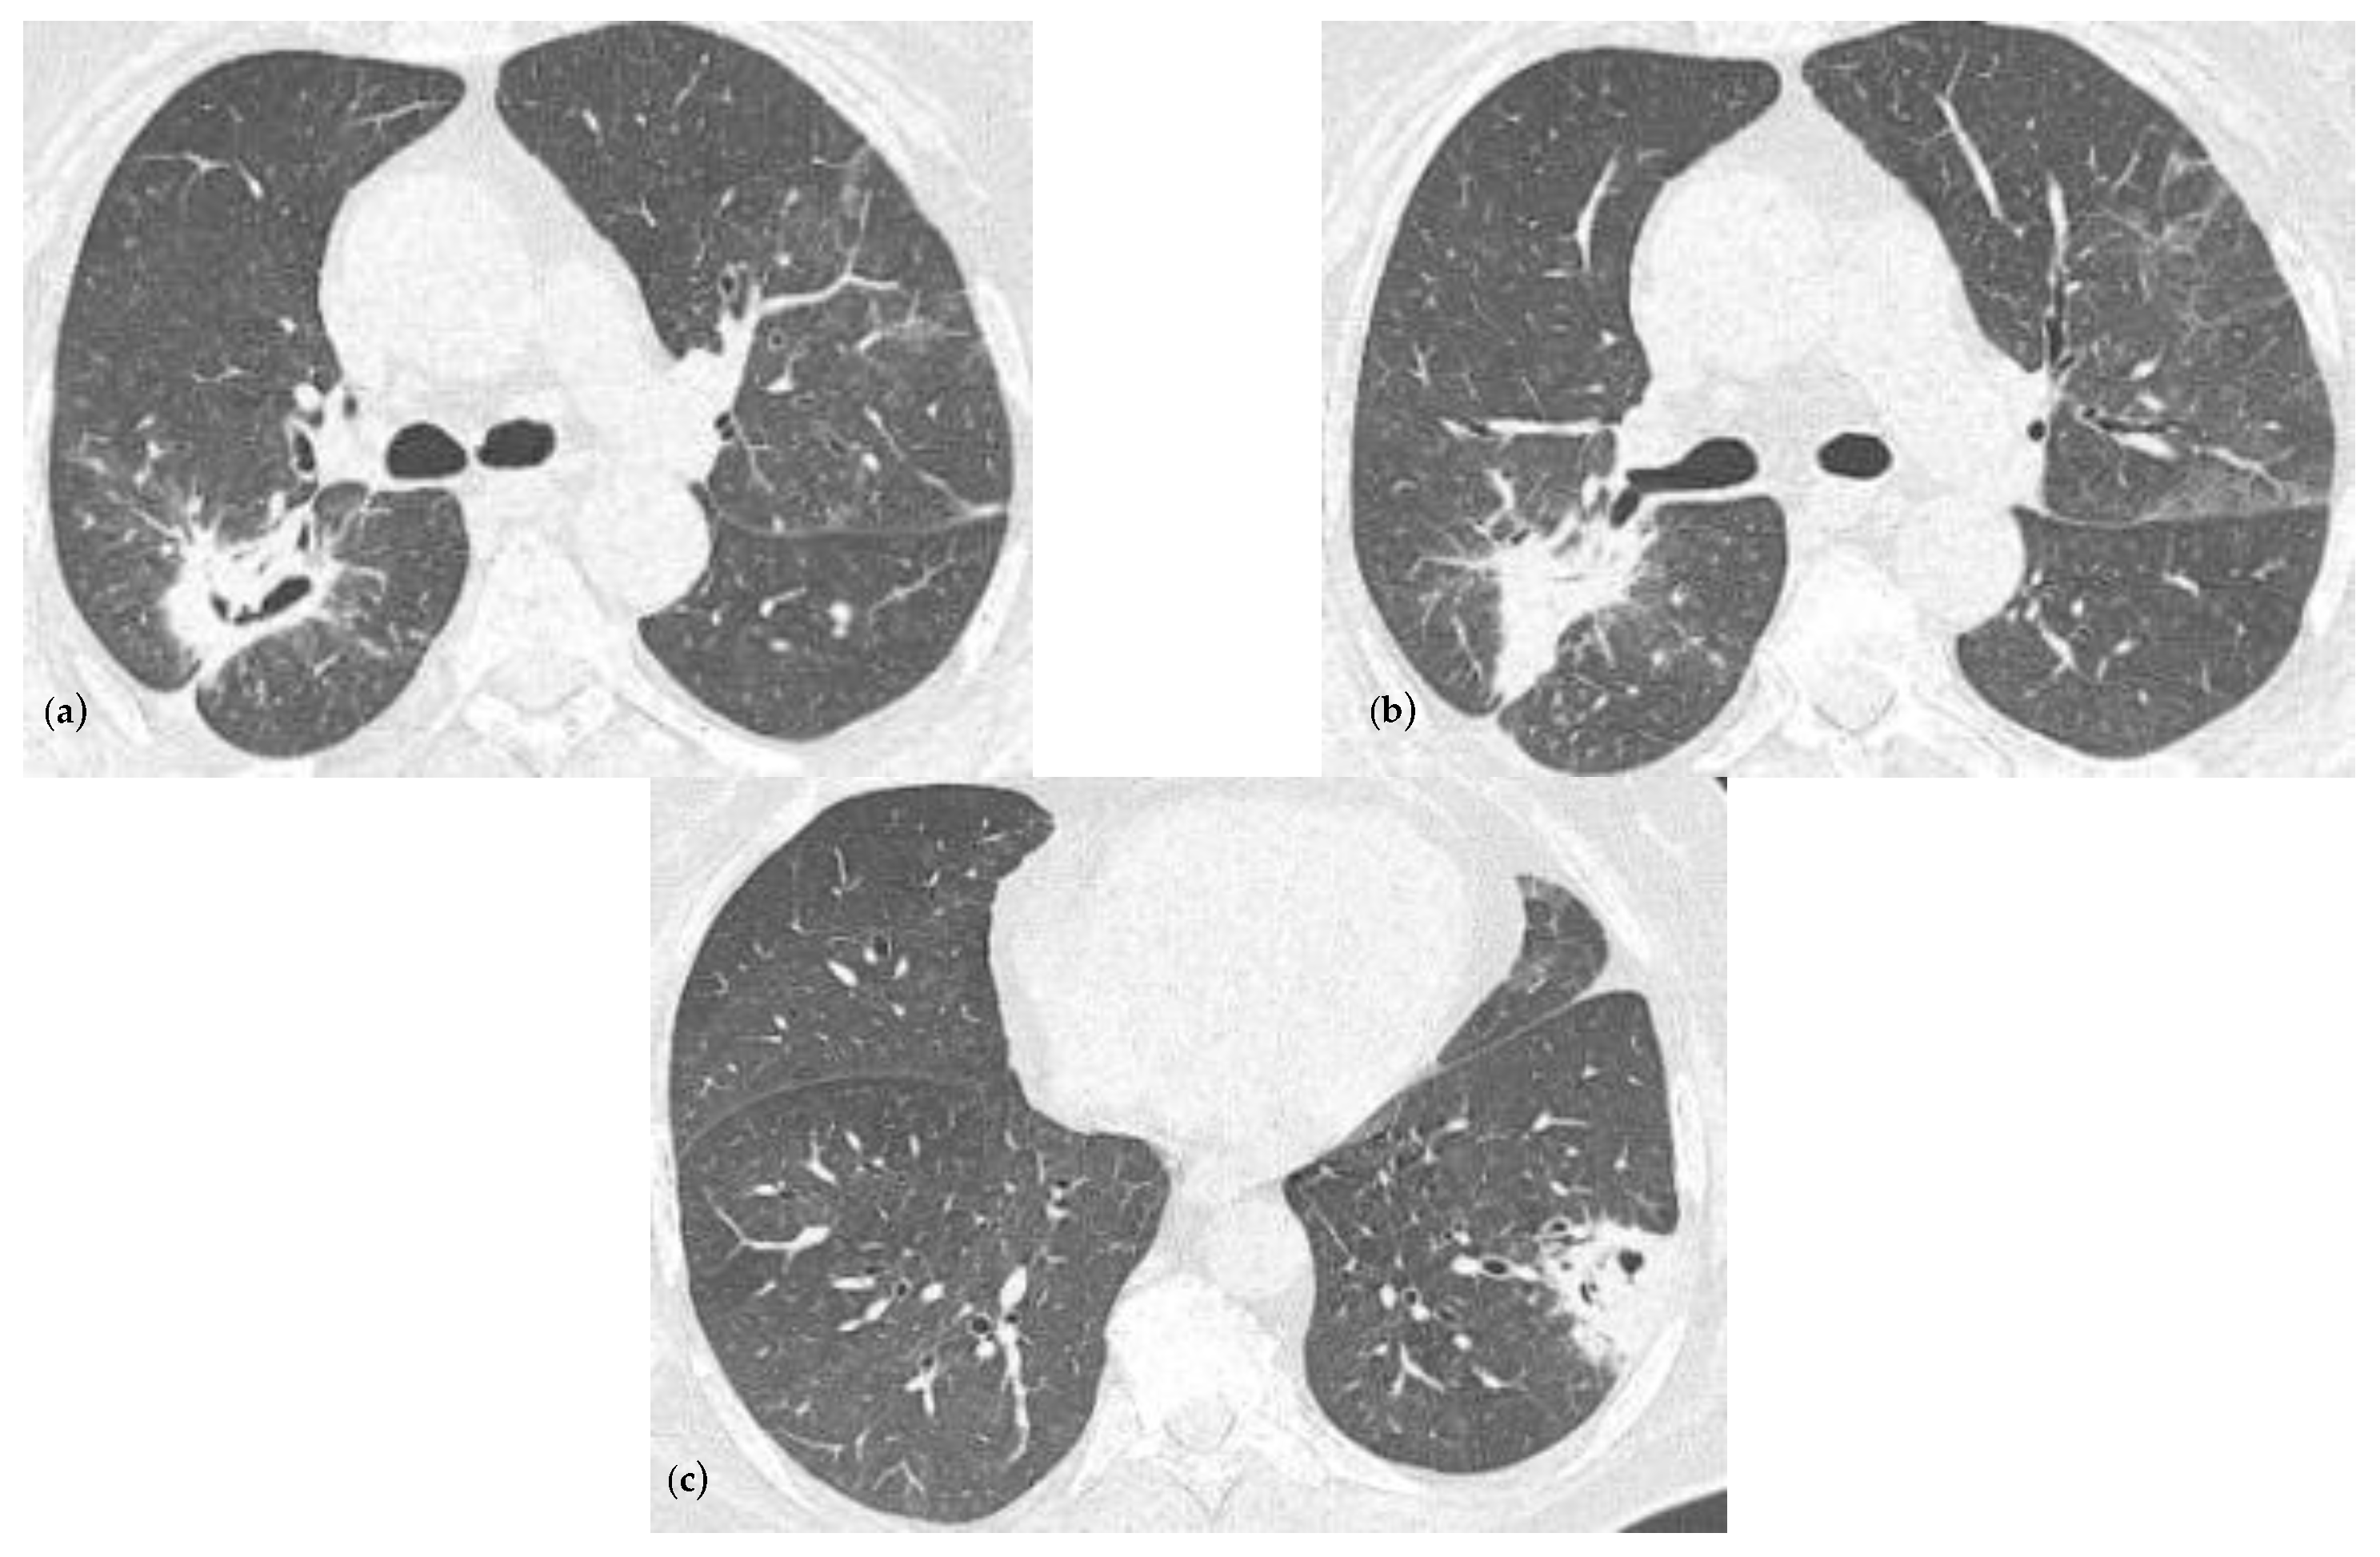

2.2. Blood Workup, Functional Tests, Bronchoscopy, and Radiological Findings

2.3. Treatment and Monitoring